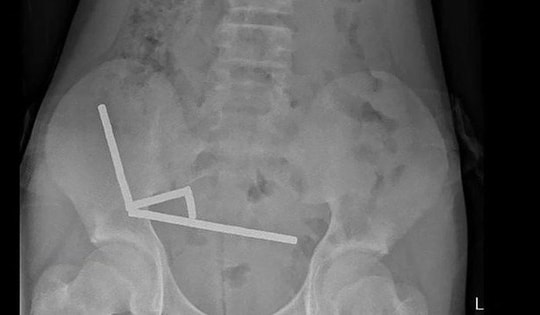

Một thiếu niên 15 tuổi phải nhập viện cấp cứu trong tình trạng đau dữ dội sau hành động bồng bột do tò mò. Thăm khám cho thấy có dị vật mắc kẹt trong cơ thể.